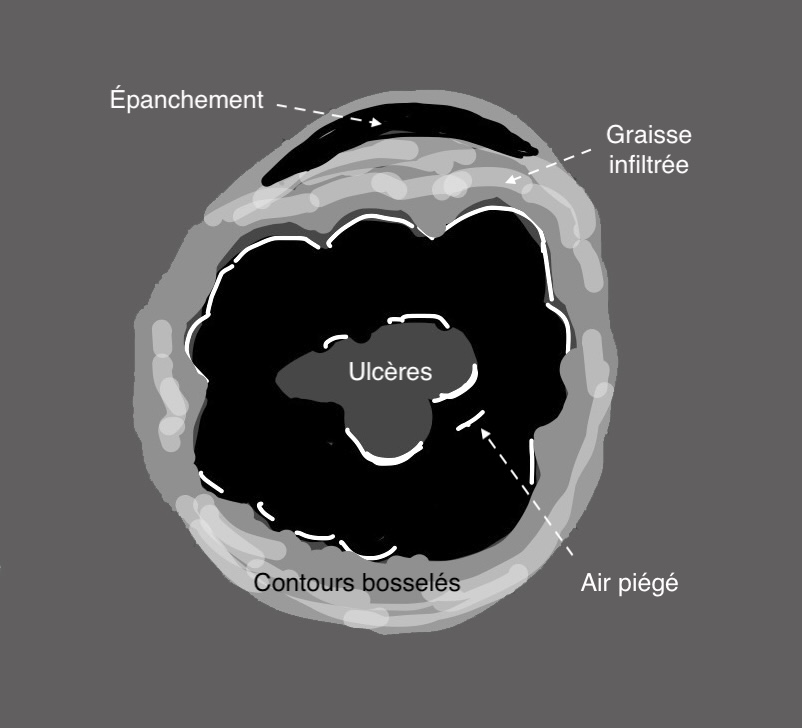

Si l’inflammation s’aggrave, on peut voir des ulcères creusants en surface et la limite externe de l’anse (classiquement rectiligne dans la RCH) devient irrégulier, bosselé.

3. L’inflammation atteint la périphérie de l’anse donc

– hyperactivité doppler intense de la paroi et de la graisse (Limberg 3)

– présence de liquide en périphérie de l’anse (perforation imminente)

La paroi du colon devient totalement déformée, en surface avec ulcères, en périphérie avec des bords externes irréguliers, la graisse est infiltrée, voire apparition d’un épanchement liquidien, signe de gravité extrême